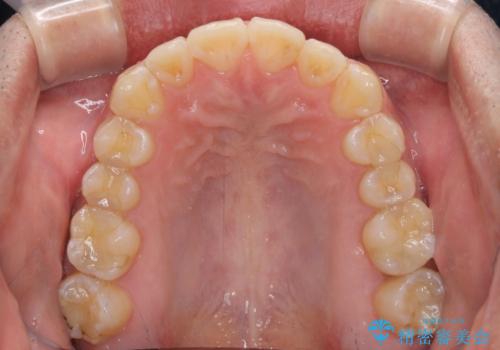

ディープバイトと叢生を解消 インビザライン矯正

- 前歯のデコボコを強い咬みしめを気にして来院された患者様です。

インビザラインを用いて、前歯の叢生を解消するとともに、ディープバイトを改善していくこととしました。

ディープバイトが改善されたことで、顎への負担が軽減され、更には上顎前歯の突出感も改善することができました。

矯正治療後には欠けてしまった修復物をセラミックインレーにて修復治療しました。